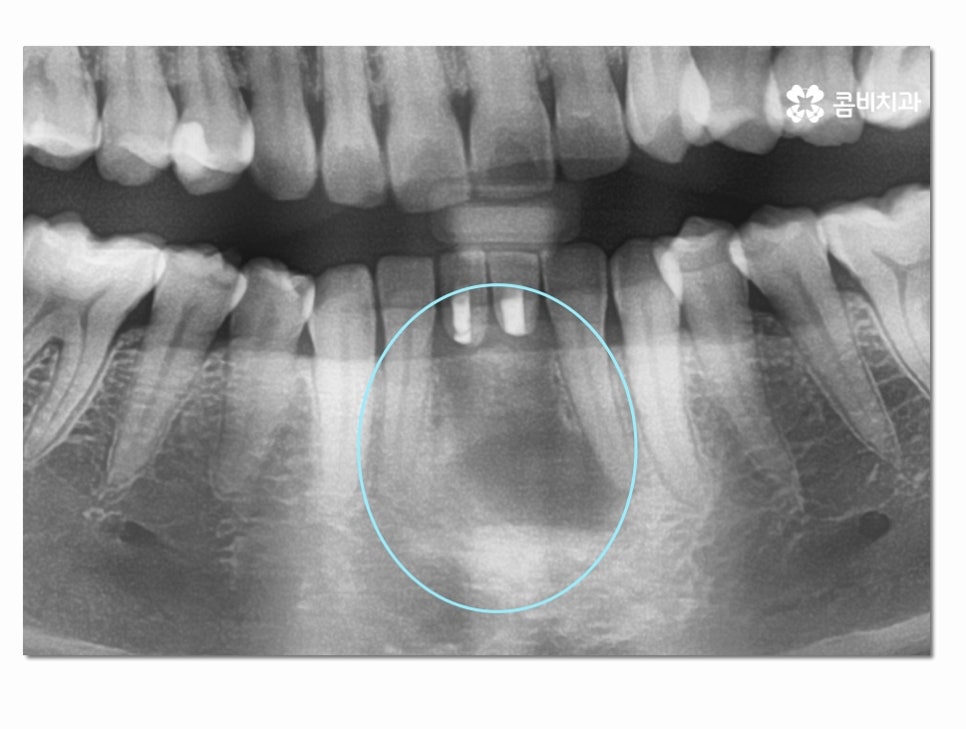

오늘은 위 이미지처럼 실제로 아랫니 임플란트 진행된

사례를 통해 시술 과정에 대해 자세하게 알아보도록 할 거예요.

위 환자분의 경우 잇몸질환이 심해져서 치아 뿌리까지

염증이 심해졌고 결국 발치까지 하게 된 사례인데

치주염이 심해지기 전까지 제대로 된 치료를 하지 않아

결국 발치까지 하게 된 경우라고 할 수 있어요.

잇몸에 염증이 방치되면 점점 심해지다가 치아 뿌리까지

손상을 입게 되는데 잇몸질환은 중기 혹은 말기까지도

큰 통증을 못 느끼는 경우도 종종 있기 때문에 주기적으로

검진과 스케일링을 하며 예방에 신경 써야 한다고 말씀드릴 수 있어요.

심한 경우에는 주변 치아에도 염증이 심해져서 여러 치아를

잃게 되는 사례도 종종 보는데 위 환자분의 경우에는

아랫니 2개까지만 멍울처럼 뿌리 끝에 염증이 심해진 상태를 볼 수 있어요.